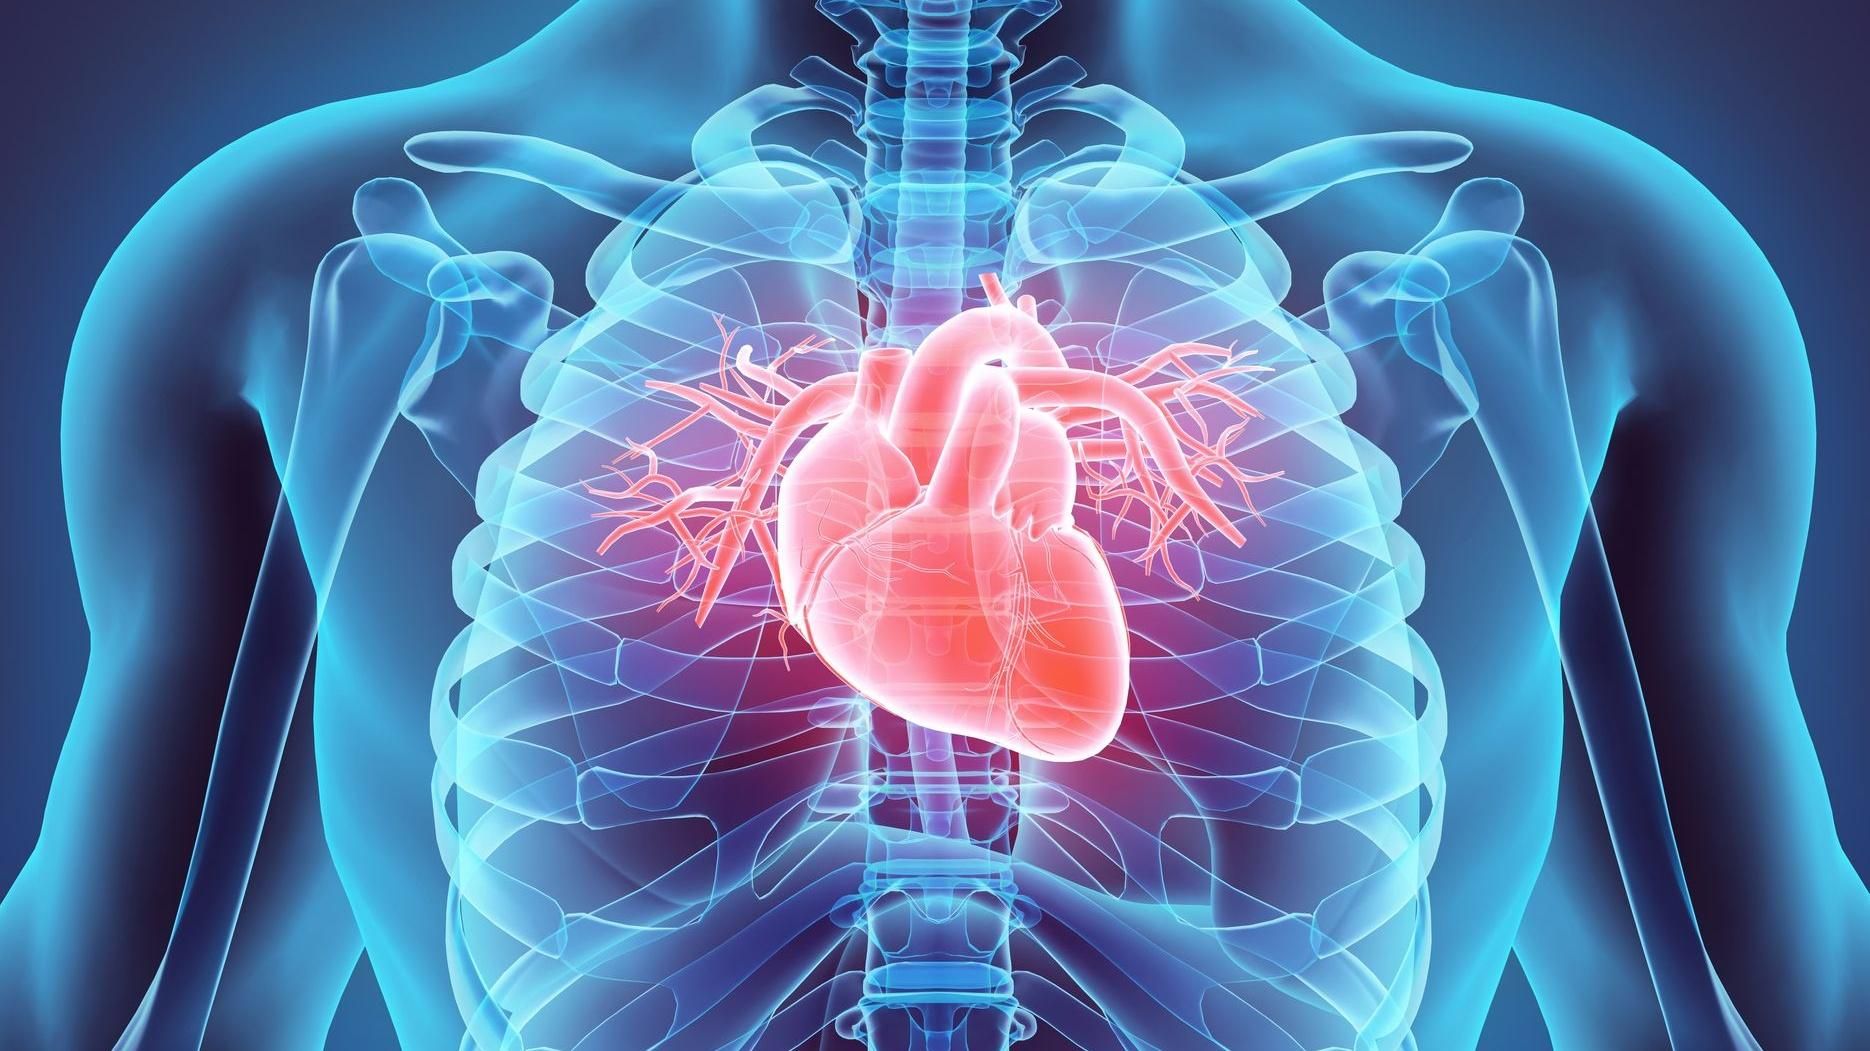

Вчені з Імперського коледжу Лондона виростили в лабораторних умовах пластир розміром 3 на 2 сантиметри, пише MedicalExpress.

Пластир містить до 50 мільйонів людських стовбурових клітин, які перетворюються на здоровий серцевий м’яз. Розробка містить речовини, які здатні відновлювати та оновлювати клітини серця.

Пластир містить до 50 мільйонів людських стовбурових клітин

Експерти вже провели дослідження над кроликами. Дослідження показали, що пластир покращує функцію серця після серцевого нападу. Після закінчення періоду до 4 тижнів детальні сканування серця показали, що лівий шлуночок серця (камера, відповідальна за перекачування крові до тіла через аорту) відновлюється без розвитку аномальних серцевих ритмів.

За словами дослідників, пластирі підживлювалися кровоносними судинами, які ростуть від серця реципієнта.